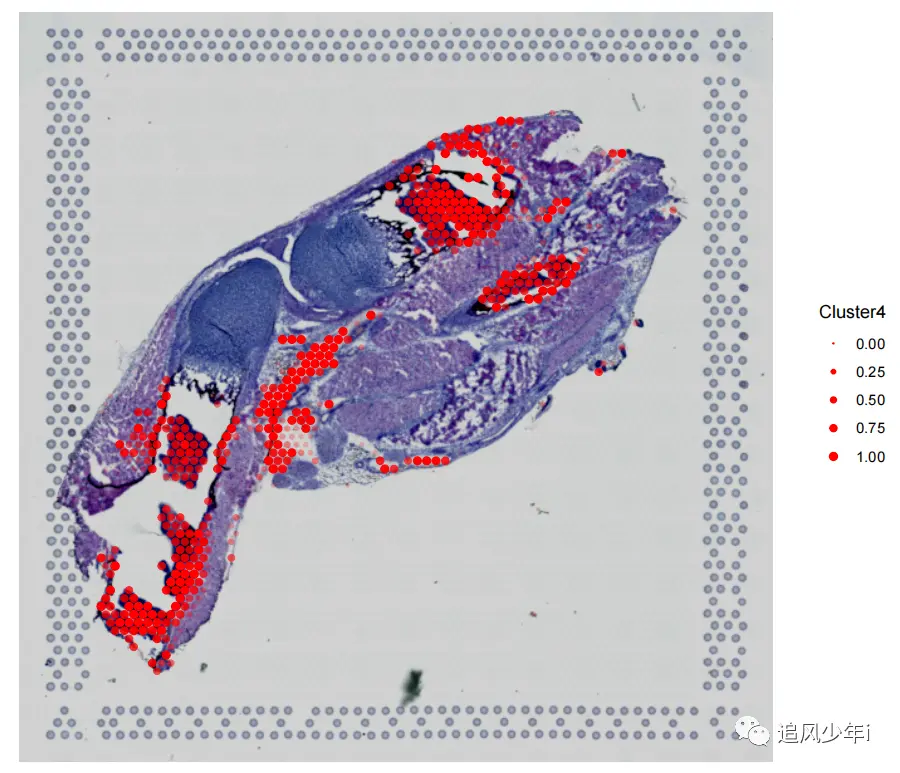

相信大多数还是利用Seurat来进行联合分析,如果用了其他软件,可以将联合的矩阵结果进行替换,我们还是以之前的结果为例,HE染色和单细胞空间联合分析的结果部分展示如下

画出来的效果如下图,颜色根据自己的喜好进行搭配

接下来颜色搭配

rel_small = 1) + ggplot2::theme_void() + ggplot2::coord_fixed(ratio = 1,xlim = NULL, ylim = NULL, expand = TRUE, clip = "on") + ggplot2::theme(legend.key.size = unit(50,'pt'),legend.title = element_text(size = 60),legend.text = element_text(size = 40)) + scale_fill_manual(values = defined_cols[1:length(cell_types_all)]))

好多了,借鉴一下第一张图的搭配

嗯,还行